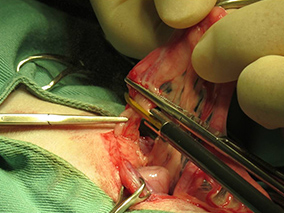

手術後の傷口です。肝臓の検査をしても避妊手術の傷跡と変わりません。

手術後も回復が早く、元気に退院していきました。